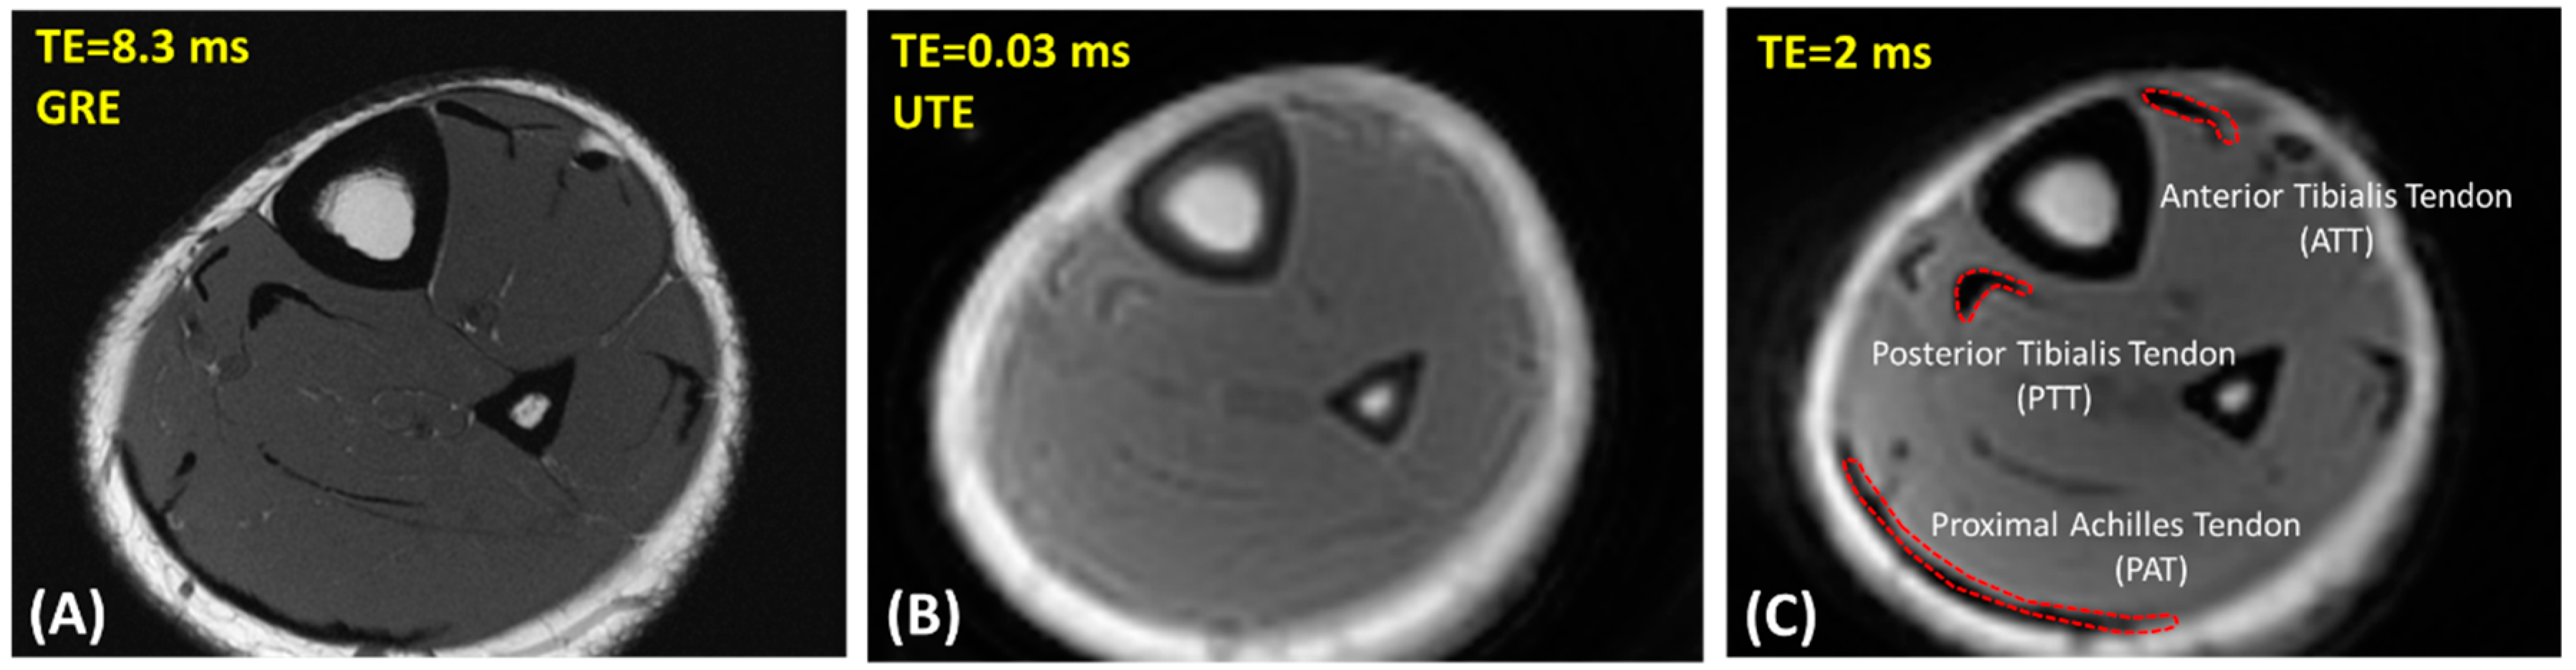

Figure 1A,B show representative axial images of the lower leg of a healthy 25-year-old female participant using clinical gradient echo (GRE) and UTE-MRI sequences, respectively.

Representative axial images of the lower leg of a healthy 25-year-old female participant using (A) clinical gradient echo (GRE) sequence (TR = 790 ms, TE = 8.3 ms, in-plane matrix = 352 × 352), (B) ultrashort echo time (UTE) Cones MRI sequence (TR = 80 ms, TE = 0.032 ms, in-plane matrix = 160 × 160), and (C) Cones MRI sequence at TE = 2 ms (TR = 80 ms, in-plane matrix = 160 × 160). Representative regions of interest (ROIs) for anterior and posterior tibialis (ATT and PTT) tendons and proximal Achilles (PAT) tendons were selected at TE = 2 ms because it provided higher contrast (indicated by red dashed boundary).

To investigate the reproducibility of the MRI data analysis, ROIs were selected by three experienced readers at the ATT, PTT, and proximal Achilles tendon (PAT). Figure 1C shows a schematic of the selected ROIs in a representative MRI image from a 25-year-old female subject (TR = 80 ms and TE = 2 ms). For quality control purposes, the ATT, PTT, and PAT ROIs selected by the readers were overseen and validated by a board-certified musculoskeletal (MSK) radiologist for the first five datasets. Intraclass correlation coefficients (ICCs) were measured for T1 and MMF comparisons across all estimations made by the three independent radiology readers.